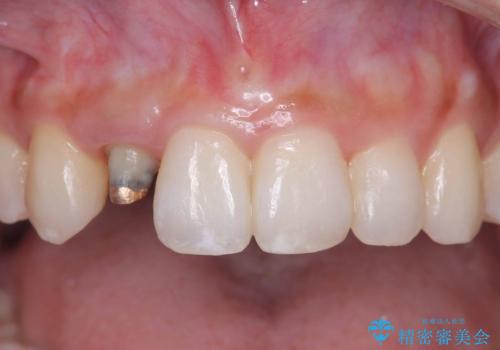

- 「前歯の見た目が気になる」を主訴に来院された患者様です。

オールセラミッククラウンで治療を行いました。

被せ物と歯の境の位置が歯肉の上に設定されており、それによって審美障害が起きていました。

歯と被せ物の境を歯肉縁下0.5㎜に設定して形成を行いオールセラミッククラウン(スペシャル)で治療を行いました。